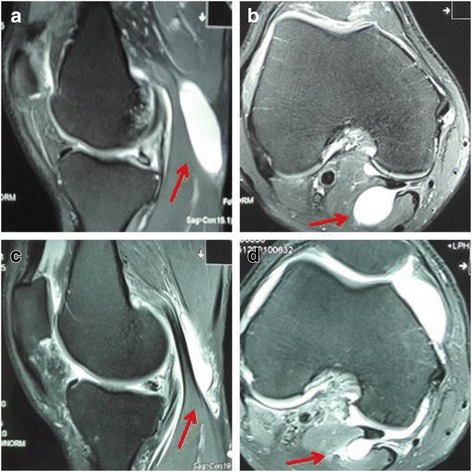

In group A, we observed that the cysts started to shrink 2 months post surgery in 13 patients (Fig. 2). In 8 patients, the cysts completely disappeared by 8 months under MRI. At the last follow-up visits, which were on average 13.7 months after the surgery, an independent clinician who was blinded to the treatment scored all patients according to the Rauschning and Lindgren classification. The patients in grade II and above were defined as recurrent patients. The recurrence rates were significantly lower in group A (3.1%) and group B (5.2%) than those in group C (40%).

Fig. 2.

Representative MRI images from group A patient, after receiving arthroscopic internal drainage. a, b Preoperative sagittal and axial views around the knee joint. c, d Postoperative sagittal and axial images at 2 months follow-up exhibited substantial shrinkage of the cyst. Red arrows indicate the popliteal cyst